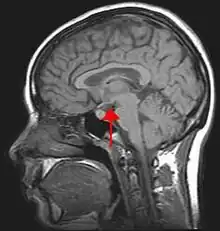

Hypothalamus

- (Anatomie) Noyau suprachiasmatique.